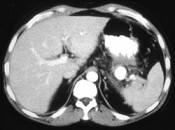

问题 男,36岁,反复剑突下胀痛5年,加重伴间断性呕血、黑便3年,有6年慢性胰腺炎病史,CT检查如图,最可能的诊断是 ( )

选项 A.脾血管瘤伴慢性胰腺炎 B.脾动脉瘤伴慢性胰腺炎 C.脾假性动脉瘤伴慢性胰腺炎 D.胰腺转移瘤伴慢性胰腺炎 E.胰腺癌伴慢性胰腺炎

答案 C